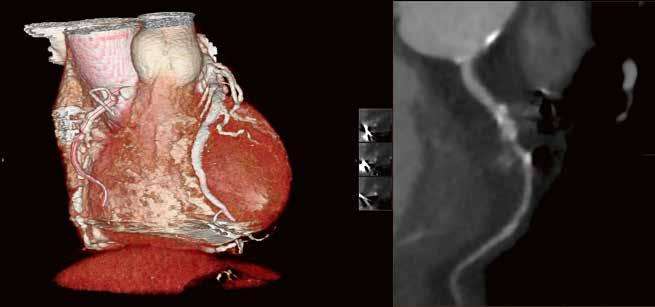

Gerade das Rauschen hat noch einmal deutlich abgenommen. In der Folge fällt die Diagnosestellung leichter. Die Begeisterung teilen viele unserer Spezialisten. So erhalten wir z. B. aus der Kardiologie die Rückmeldung, dass unsere Abteilung mit dem Hightech-CT im Vergleich zu anderen radiologischen Untersuchungen die beste Bildgebung vorweisen kann. Gerade bei Fällen, wo es um kleine Strukturen geht, Beispiel „Revaskularisierung chronischer Koronarobstruktionen“: Hier gilt unsere Bildgebung für die Planung der Rekanalisationen von chronischen Koronarverschlüssen (CTO) mittlerweile als Standard. Wir bekommen aus der Kardiologie ausschließlich Lob und eine große Zufriedenheit zurückgespiegelt. Bei der Kardiodiagnostik wird der Volumen-CT absolut priorisiert.

Die Herzuntersuchungen sind damit in unserer Abteilung auf einem Niveau angekommen, das – Stand heute – schwer zu toppen ist.

Die notwendige Dosis – schon beim zweiten Kardio-CT weniger als 1 Millisievert – ist durchgehend sehr gering. Dank der kurzen Scanzeit und der hohen zeitlichen Auflösung untersuchen wir heute selbst Herzen im Volumen-CT, bei denen wir früher gezögert hätten. So z. B. bei dem Fall

der 64-jährigen arrhythmisch Patientin mit V. a. KHK (Fall Nr. 2).

64-jährige Patientin, Troponinämie. V. a. KHK. Frage nach KHK. 55 kg, DLP 43,9 mGy*cm, CTDI vol. 3,7 mGy.

RCA Rechter Hauptstamm Linker Hauptstamm Peripherer RIVA (AHA Seg. 8 + 10) Fall 2: RIVA RCX

76-jähriger Patient: geplante Rekanalisation bei CTO (chronic total occlusion) der RCA. Planungs-CT. CTDI vol.

3,1 mGy; DLP 37,3 mGy*cm, 80 kV, 76 – 81 BpM (763 ms), 1 Halbscan, 3 5– 5 5 %.